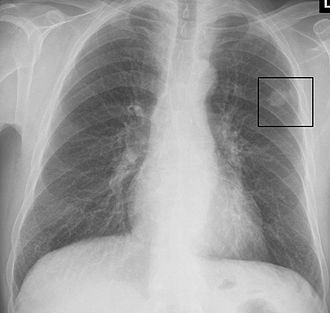

Jedna od prvih pretraga u osobe sa simptomima koji bi mogli ukazivati na karcinom pluća je rentgen prsišta. Njime se može otkriti jasna tumorska masa, proširenje medijastiuma (koje ukazuje na tumorsko zahvaćanje limfnih čvorova u tom području), atelektazu (kolaps pluća), konsolidaciju (pneumoniju) ili pleuralni izljev.[2] CT se tipično koristi za dobivanje podrobnijih podataka o vrsti i proširenosti bolesti. Bronhoskopija ili biopsija pod kontrolom CT-a se često koristi za uzimanje uzorka tkiva tumora u svrhu patohistološke pretrage.[10]

Na rentgenskoj slici pluća karcinom pluća se često očituje kao pojedinačni čvor u plućima. Međutim, u tom je slučaju diferencijalna dijagnoza vrlo široka. Mnoge druge bolesti mogu se očitovati na isti način, uključujući tuberkulozu, gljivične infekcije, metastazu raka iz nekog drugog primarnog sijela i organizirajuću pneumoniju. Manje učestali uzroci pojedinačnog čvora u plućima su hamartomi, bronhogene ciste, adenomi, arteriovenska malformacija, plućna sekvestracija, reumatoidni čvorovi, Wegenerova granulomatoza ili limfom.[42] Rak pluća može biti i slučajni nalaz, na retgenskoj slici ili CT-u pluća učinjenima iz nekog drugog razloga.[43] Konačna dijagnoza karcinoma pluća postavlja se na osnovi histološke pretrage tkiva koje je sumnjivo na osnovi kliničkih i rentgenskih osobina.[1]